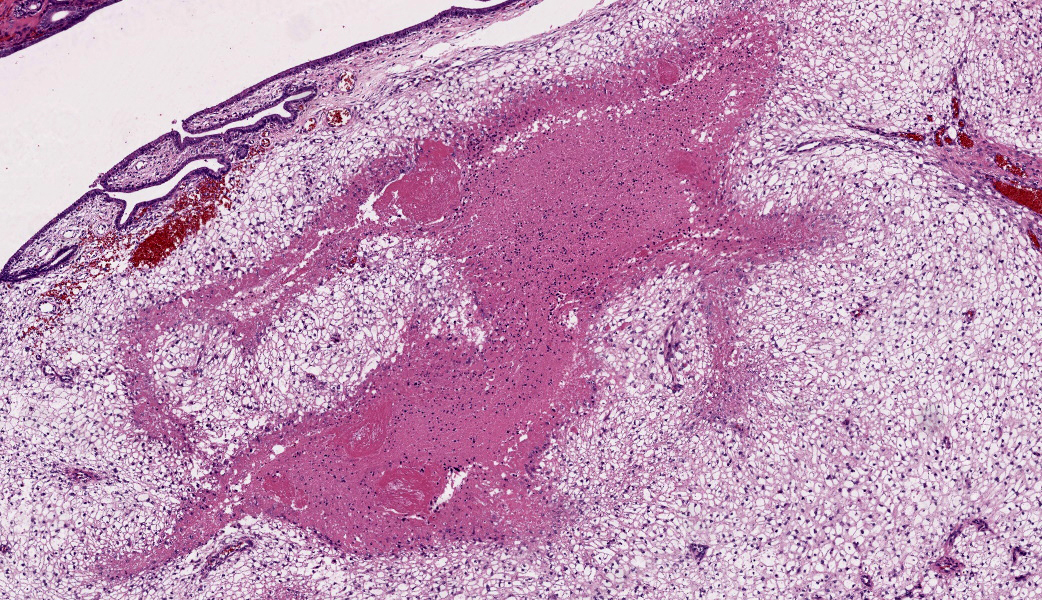

The endometrium on the mesometrial side of the uterus proliferated with the formation of large nodules and numerous polyps. The surface of the nodules and polyps was covered by endometrial epithelium, however, approximately 50% of the epithelium were eroded. The polyps and nodule contained numerous blood vessels with normal endothelium, along with cells that resembled large-vacuolated decidual cells, arranged in sheets. The decidual cells had distinct cell boundaries, a round shape, abundant transparent cytoplasm, and nuclei ranging from oval to irregular shapes. Mitotic figures were also occasionally observed. Just beneath the endometrial epithelium, the decidual cells exhibited a spindle-shaped morphology. (Fig.1 and 2)On the antimesometrial side of the uterine, endometrial hyperplasia was mild, decidual cells in the endometrial stroma were sparse, and proliferation of huge giant cells resembling trophoblast was prominent. The huge giant cells displayed a variety of morphologies, including round, spindle, to pleomorphic, with notably large, highly atypical nuclei and abundant cytoplasm. Multinucleated giant cells were also observed.The immunohistochemical analysis demonstrated that normal endometrial epithelium is positive for progesterone receptor (PgR), keratin AE1/AE3, and CAM5.2, and negative for CD10, SMA and desmin. Normal endometrial stromal cell is positive for PgR and CD10, and negative for keratin AE1/AE3, CAM5.2, SMA and desmin. Decidual cell is positive for PgR and CD10, and negative for keratin AE1/AE3, CAM5.2, SMA and desmin. The huge giant cells exhibited positive for keratin AE1/AE3, CAM5.2 and CD10, and negative staining for PgR, SMA and desmin.

The case was characterized by the proliferation of vacuolated cells in the endometrial stroma covered by normal endometrial epithelium.?In the presence of an embryo and normal placental formation, trophoblasts attached to the outer surface of the endometrial epithelial cells.3,6,7 However, in this case, the absence of trophoblast cell proliferation clearly indicates that normal placental formation has not occurred. It can thus be concluded that only vacuolated cells of maternal origin are proliferating. The vacuolated cells exhibited a morphology similar to that of decidual cells during normal placental formation and frequently contained PAS-positive granules, further supporting this interpretation. Immunohistochemical staining revealed positivity for CD10, negativity for keratin and positivity for progesterone receptors. These findings are consistent with the staining pattern of endometrial stromal cells and provide further confirmation of the origin of these cells from the endometrial stroma. Sensitization by progesterone is necessary for the initiation of decidualization of the endometrial stroma, and stable progesterone activity is necessary for the stable existence of decidual cells.2 In this case, the expression of progesterone in both the endometrial stroma and epithelium indicates that a decidual reaction has occurred overall.

In contrast, numerous giant cells were observed on the obplacental (antimesometrial) region. These giant cells are similar to obplacental giant cells formed in the pregnant uterus of rabbits with regard to both cell morphology and location. 1 The origin of these cells remains unclear. The absence of obvious trophoblasts and the formation of giant cells in the endometrial stroma beneath the normal endometrial epithelium suggest a uterine origin. However, immunostaining revealed positivity for CK and CAM5.2 (epithelial marker) and CD10 (positive for endometrial stromal cell), and negative for PgR (positive for both endometrial epithelial and stromal cell), which did not correspond with the staining patterns of endometrial epithelial or stromal cells. Consequently, it was not possible to ascertain their origin with any degree of certainty.